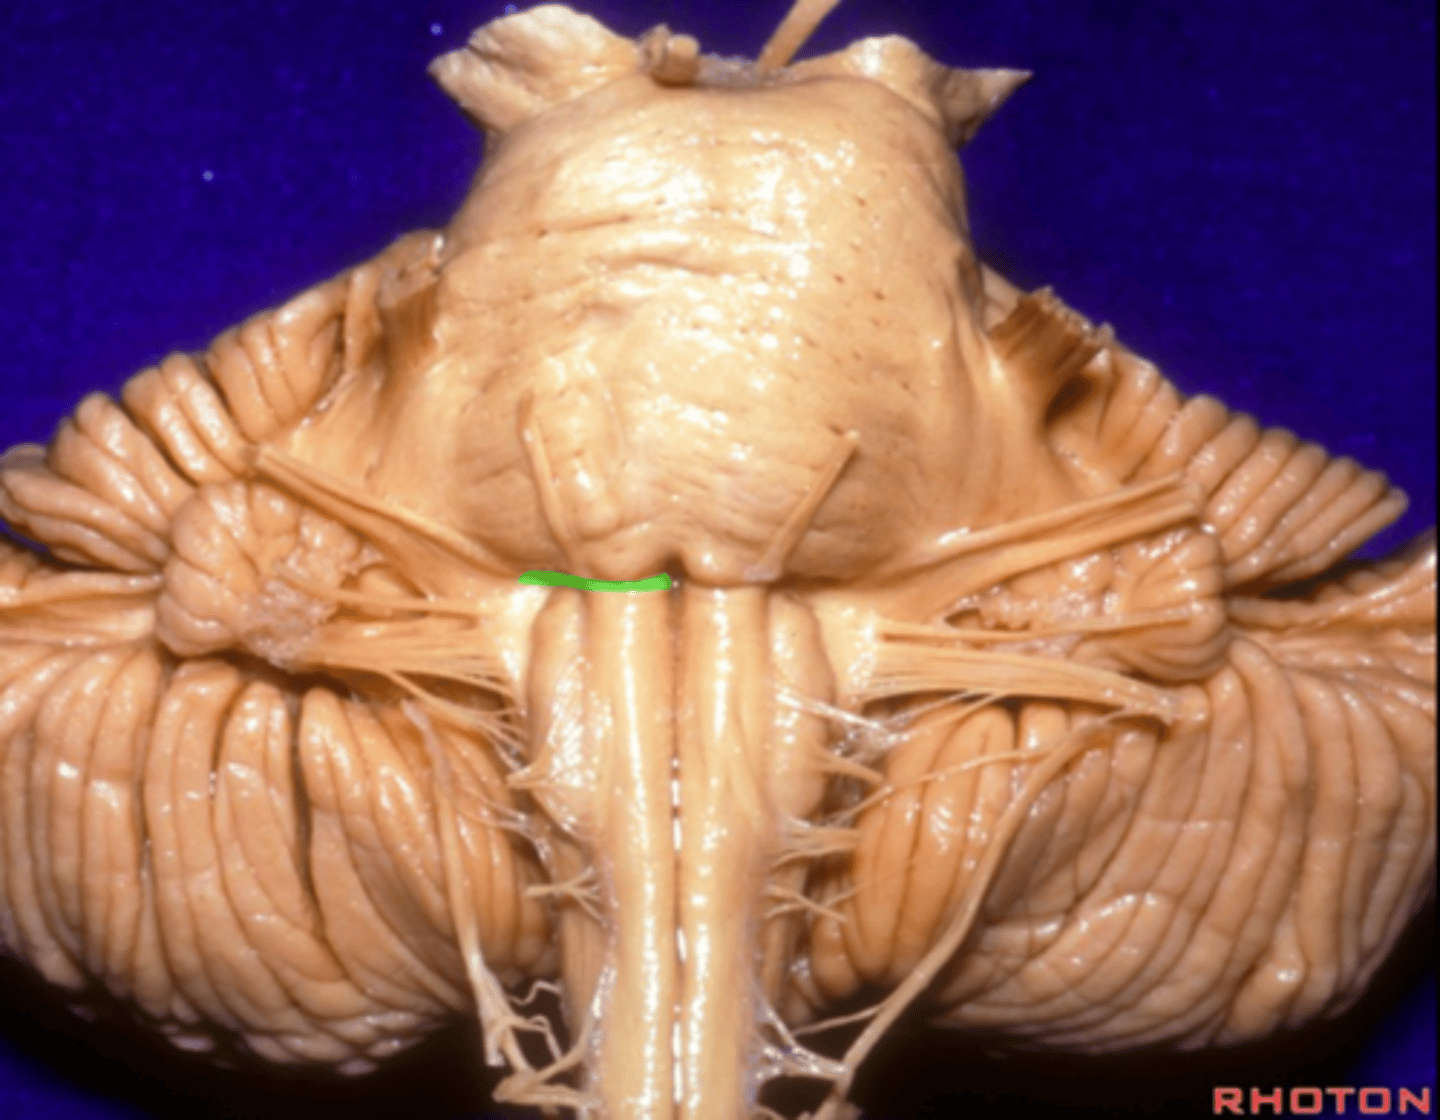

white matter stalks that connect the medulla to the cerebellum

**these help to form the lateral walls of the caudal portion of the 4th ventricle

inferior cerebellar peduncles

superior ends of the medial paired ridges of tissue on the dorsal aspect of the closed portion of the medulla, formed by namesake nuclei

gracilis tubercles

superior ends of the lateral paired ridges of tissue on the dorsal aspect of the closed portion of the medulla, formed by namesake nuclei

cuneatus tubercles

V-shaped boundary of the caudal aspect of the 4th ventricle that marks the boundary between the open and closed portions of the medulla

obex

inferior angle of the floor of the 4th ventricle

obex

fibers that run horizontally in the central region of the rhomboid fossa of the 4th ventricle

stria medullares

area that helps to make the walls of the obex and is thought to be the "vomit trigger"

area postrema

opening in the caudal aspect of the inferior medullary velum that allows CSF from the 4th ventricle to flow into the cisterna magna of the subarachnoid space

foramen of Magendie (or median aperture)

What mostly forms the lateral walls of the 4th ventricle?

inferior cerebellar peduncles and choroid plexus

openings in the 4th ventricle that allows CSF to flow from the 4th ventricle into the pontine cistern of the subarachnoid space

foramen of von Luschka (or lateral apertures)